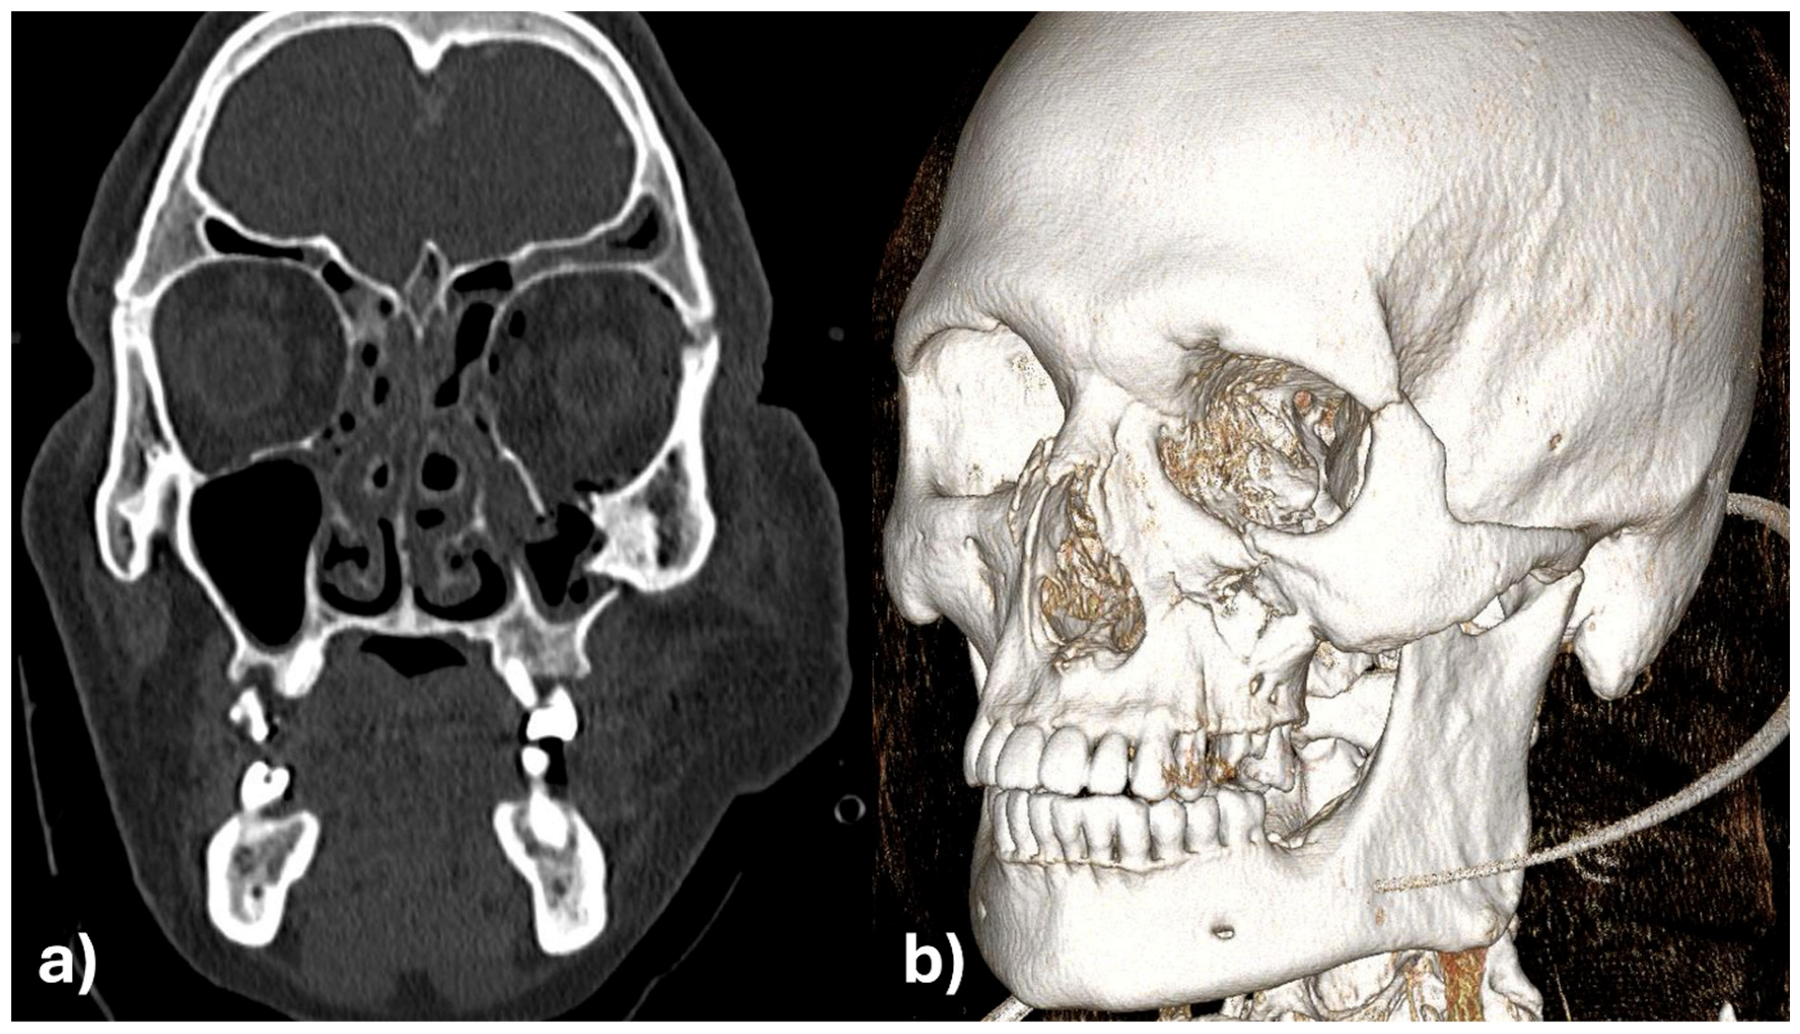

The initial assessment showed facial asymmetry, periorbital swelling and diplopia. Clinical examination revealed depression of the zygomatic arch on the left side and restricted ocular movement. CT scan confirmed fractures of the zygomatic-maxillary-orbital complex, with significant displacement of the zygomatic bone and herniation of orbital contents (Figure 1).

Figure 1. Zygomatic-maxillary-orbital-complex fracture of the left side. (a) Coronal view, (b) 3D reconstruction.